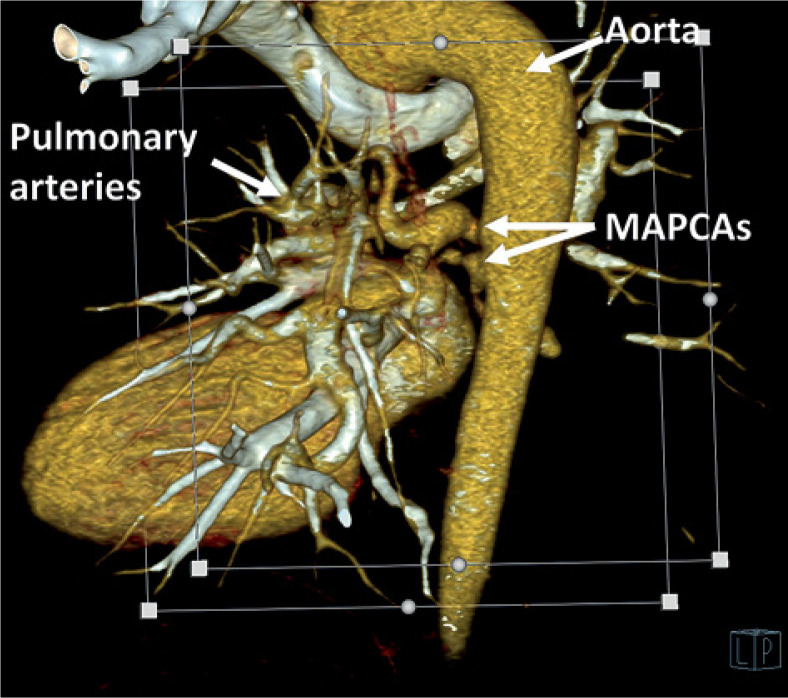

Purpose: Major aortopulmonary collateral arteries (MAPCAs) are rare congenital anomalies with significant clinical implications, often associated with congenital heart diseases like tetralogy of Fallot (TOF) and pulmonary atresia (PA). This study aimed to investigate the clinical, echocardiographic, and radiologic characteristics of MAPCAs in patients with congenital heart diseases admitted to our clinic between 2016 and 2023.

Material and methods: A retrospective analysis of 46 cases was conducted using chest computed tomography exams performed on a dual-source 128-slice CT scanner. Clinical data and radiologic characteristics were collected and analysed.

Results: The study revealed a strong correlation between congenital heart diseases and the presence of MAPCAs, with TOF, PA, and ventricular septal defect (VSD) being the most common, and it indicated that these collaterals may exist with non-diagnosed congenital heart disease. Tricuspid regurgitation and aortic insufficiency were the predominant echocardiographic findings. Radiologically, MAPCAs primarily originated from the descending aorta (type II) in 85% of cases, and their sizes ranged from ≤ 3 mm to > 10 mm, with an average of 5 mm.